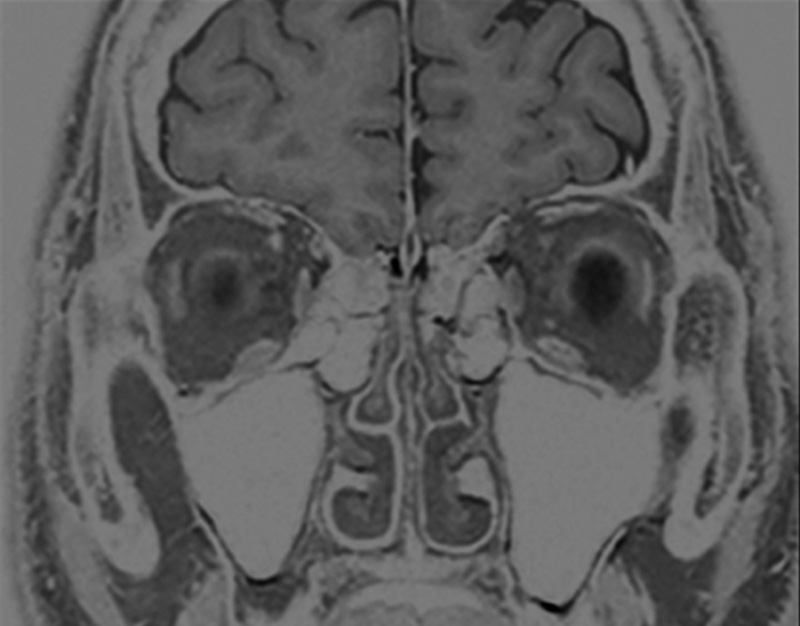

Cor T2w for hippocampus

Example of a high-resolution image of the hippocampus using Precise IQ Engine (PIQE). The original image is 256 matrix with low resolution and high signal-to-noise ratio (SNR).

Even though the scan time is reasonably short and the slice thickness is as thin as 2 mm, the image is clear and demonstrates good contrast.